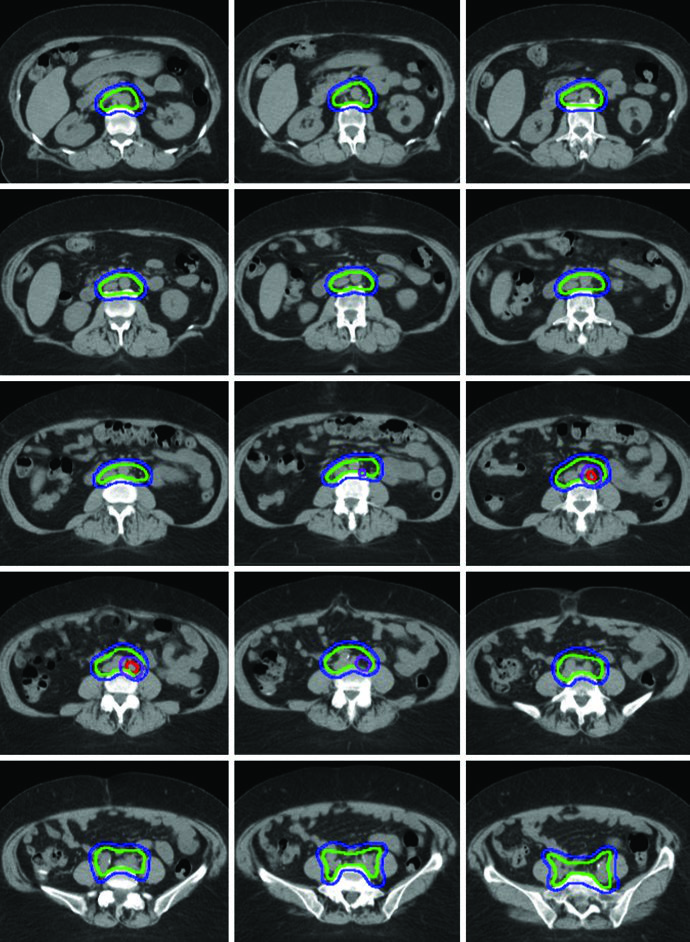

Postoperative delineation for cervical and uterine cancer patients utilizes multiple CTVs — CTV1, CTV2, and CTV3 — allowing anisotropic CTV-to-PTV expansions. Each component has a distinct anatomic role and margin, as defined in the TIME-C randomized clinical trial.

| CTV1 | Vaginal cuff, including fat and soft tissue anterior and posterior to the cuff between the bladder and rectum | 15 mm |

| CTV2 | Paravaginal/parametrial tissues, proximal vagina (excluding the cuff) | 10 mm |

| CTV3 | Common iliac, external iliac, and internal iliac nodal regions — pelvic vessels + 7 mm expansion (excluding bone, muscle, and bowel), soft tissues between internal and external iliac vessels, presacral nodes (soft tissues anterior to S1-S2, minimum 1.0 cm). Upper extent: 7 mm inferior to L4-5 interspace. Lower extent: superior aspect of femoral head | 7 mm |

Final PTV Composition

PTVs are created for each CTV with different margins — 15 mm for CTV1, 10 mm for CTV2, and 7 mm for CTV3 — reflecting the degree of internal organ motion and setup uncertainty for each component. The final PTV for treatment planning is generated by combining the individual PTVs: PTV = PTV1 ∪ PTV2 ∪ PTV3.

When using the ITV approach, CTV1 and CTV2 should be contoured on both empty and full bladder scans and fused to generate the ITV. A 7 mm expansion on the ITV generates the PTV, which is combined with PTV3 for the final PTV. This strategy is particularly important because the vaginal cuff and paravaginal tissues undergo significant displacement with bladder filling variations.

A boost of 5-15 Gy may be added for gross nodal disease or parametrial involvement, delivered either sequentially or as a simultaneous integrated boost (SIB). The textbook illustrates a patient with FIGO stage IB endometrioid adenocarcinoma, post robotic-assisted laparoscopic hysterectomy, who had an enlarged para-aortic lymph node found at CT simulation. She was treated with extended field IMRT using an ITV technique. The superior border of CTV3 was modified to include the renal hilum, the GTV of gross nodal disease was contoured, and it received a planned SIB boost of 5940 cGy with 4760 cGy in 28 fractions to the remaining nodes.